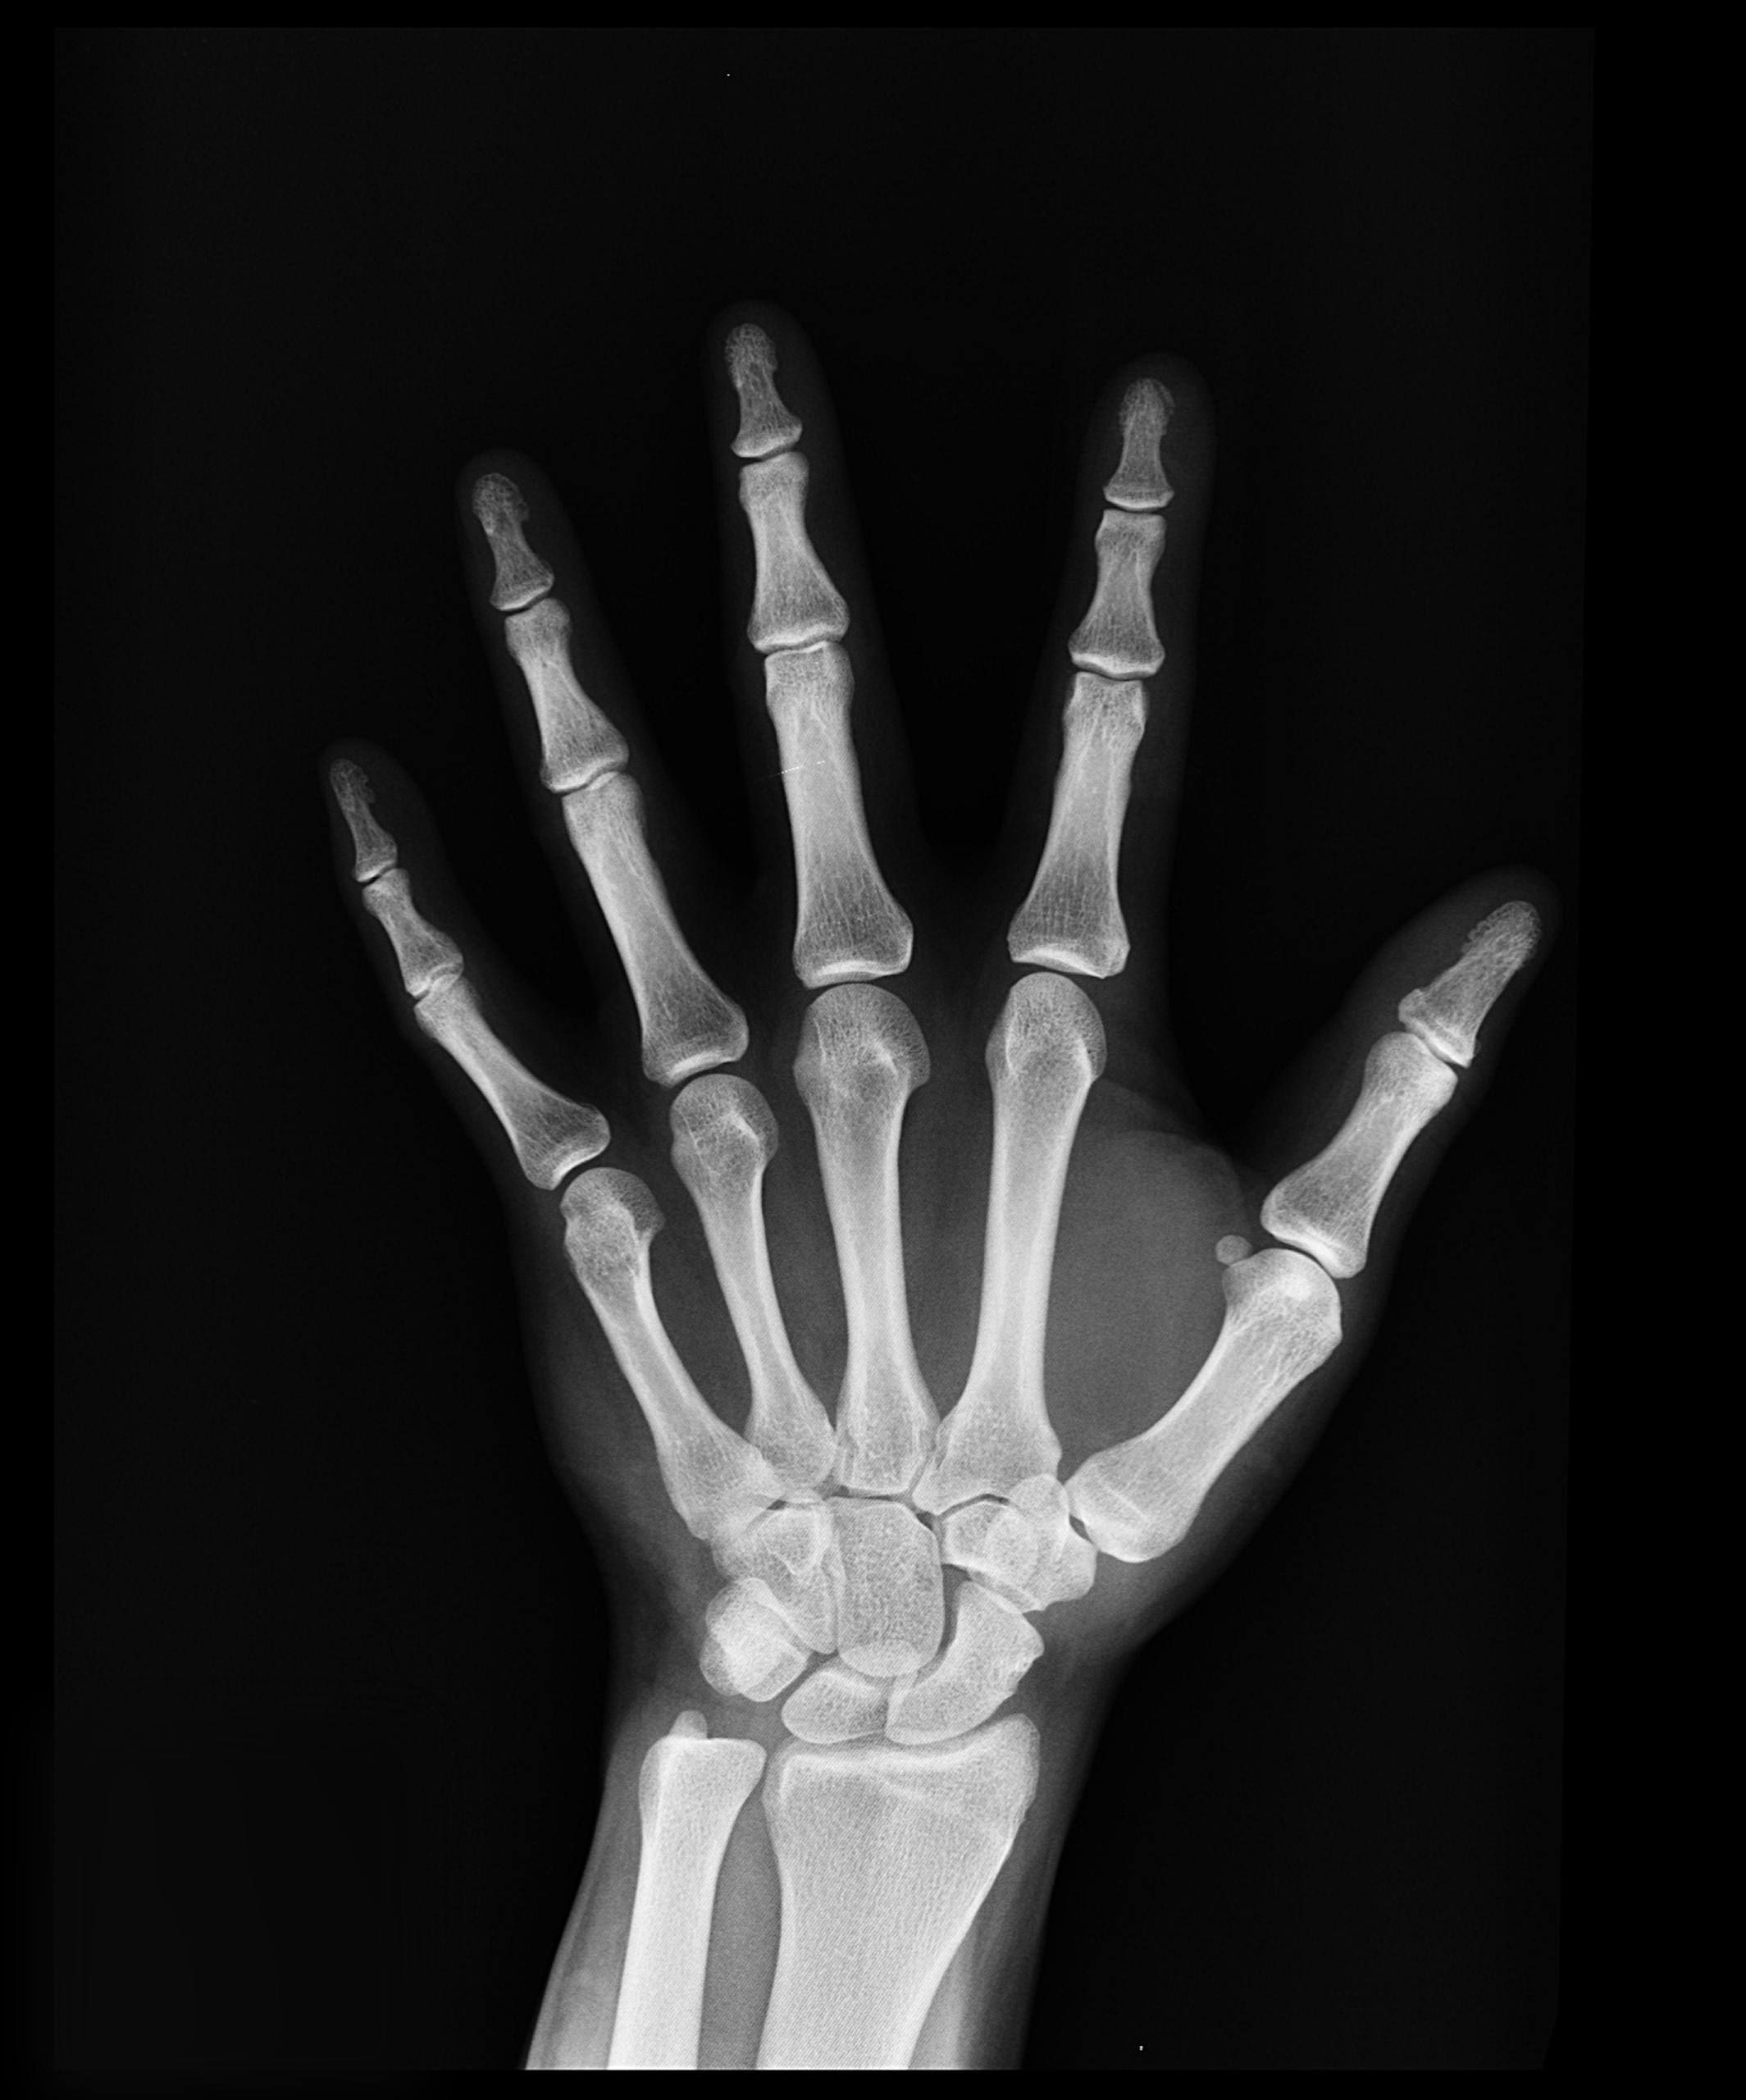

Understanding Osteoporosis and Why It Matters

Osteoporosis is a disease where bones become weak, brittle, and more likely to fracture. It’s often called the “silent disease” because bone loss occurs gradually and without obvious symptoms until a fracture happens.